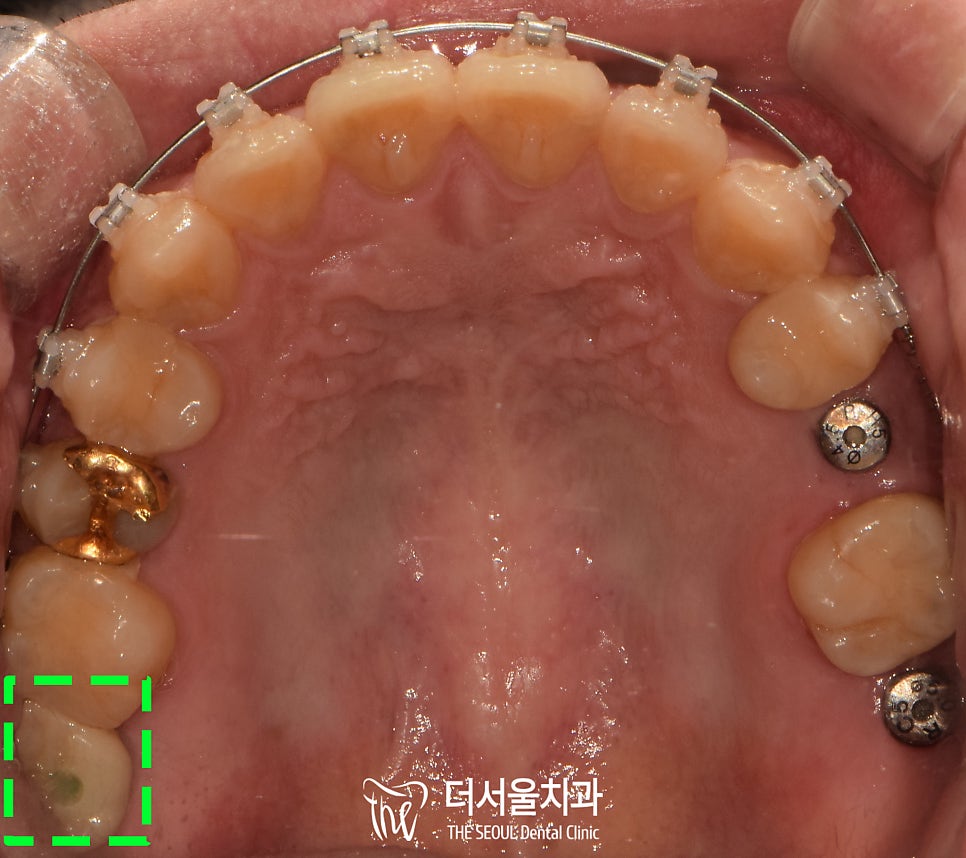

교합면을보면 뭔가 좁다는 느낌을 받을 수 있는데,

치아를 상실한지 조금 오래 되었다 하셨습니다.

그래서 25번 위치는 픽스처를 식립하기

힘든 상태였습니다.

계획에 따라 장치를 부착하여

25번 픽스처 식립을 위한

공간 형성 치료를 진행합니다.